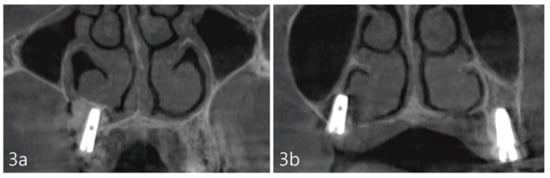

For post-operative management, medications were prescribed, including systemic antibiotics, Cefradine 500 mg twice a day for 14 days (Yuhan Pharmaceutical Co., Ltd., Seoul, Republic of Korea), and non-steroidal anti-inflammatory drug Anaprox 275 mg (Chong Kun Dang Pharmaceutical Co., Seoul, Republic of Korea), as needed. The patient was instructed to maintain oral hygiene with the use of 0.12% chlorhexidine solution (Hexamedine, Bukwang Pharmaceutical, Seoul, Republic of Korea) BID for 14 days. The patient was cautioned against expelling nasal mucus forcefully through her nose for 7 days and was also advised to keep the surgical area clean. Prior to her dismissal, a CBCT was acquired to obtain the post-operative view of the surgical procedure, including the location of the implants in relation to the inferior meatus (Figure 3a,b).

Figure 3. (a). Coronal views of the CBCT immediately after the implant placement showing adequate elevation and grafting with a well-defined periphery of the grafted site. (b). At site #2 tooth, the implant was placed with partial involvement of the lateral wall of the nasal cavity.

The case report presented here demonstrates no clear perforations with uneventful healing for the patient. Immediately following the surgery, CBCT analysis of the implant placement and bone augmentation demonstrated adequate elevation and grafting in the lateral nasal wall of the inferior meatus (Figure 3a,b). Figure 3a specifically demonstrates a well-defined periphery of the grafted site along the implant placed at site #4. The implant at site #2 was placed utilizing the transcrestal approach and depicts partial bony engagement of the lateral wall (Figure 3b). The surgical site healed uneventfully and no early or late complications were documented. Six months post-surgery, radiographic and clinical examination revealed stable implants engaged with the augmented bone during the uncovering. The bone biopsy harvested at implant uncovering and the placement of healing abutments were evaluated morphometrically. The core-stained slides were examined and depicted in entirety in Figure 5a, at 1× resolution. Figure 5b at 10× resolution, provides a detailed view of the newly formed bone and residual calcium phosphate particles. The newly depicted bone demonstrates osteocytes encased within and associated active osteoclast and osteoblasts cells. The actively remodeled sites are flanked by osteoid deposits and residue calcium phosphate particles. Histologically, the site does not demonstrate any necrotic bone, bacterial debris, or invasion. The site demonstrates active bone remodeling, indicating vital bone undergoing bone turnover where the biphasic calcium phosphate is eventually resorbed and replaced by new bone. Furthermore, clinical and radiographical observations reveal no associated complications such as marginal bone loss around the implants placed at sites #2 or #4 or soft tissue ingress, etc. (Figure 6a–c). The patient’s airways continue to remain patent, with no clinical complication or masticatory problems reported in subsequent follow-ups.